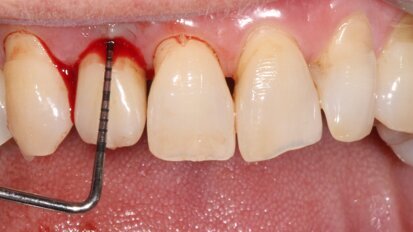

Progettazione della terapia chirurgica dell’eruzione passiva alterata: l’evoluzione digitale

L’eruzione passiva alterata rappresenta una condizione molto frequente nei giovani e negli adulti ed è stata descritta ampiamente in letteratura sia per ...